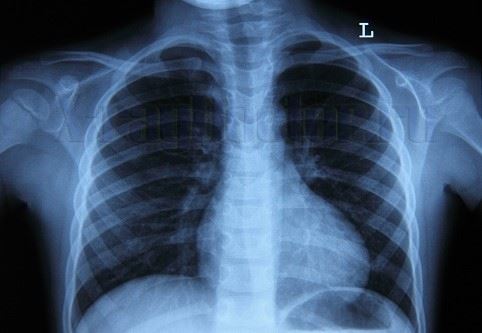

Итак, возьмем рентгеновский снимок легких и попробуем отличить нормальные анатомические структуры от патологических.

Норма на рентгене грудной клетки:

- черные легочные поля (симметрично с обеих сторон);

- белая тень посередине (сердце)

- серая костная структура (ребра, плечевые суставы);

- белые дугообразные «купола» (снизу под легочными полями, симметрично);

- позвоночный столб посередине.

Как обнаружить патологию на рентгенограмме:

- дополнительные белые тени на фоне легочных полей;

- увеличение ширины или деформация контуров нормальных анатомических структур (грудины, сердца, позвоночника);

- кольцевидные полости в легочных полях;

- белые горизонтальные уровни в нижних отделах плевральной полости.